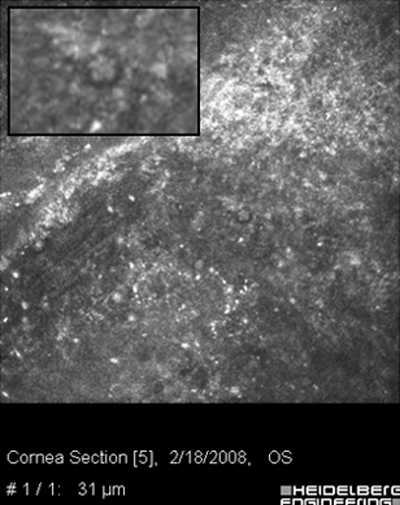

Ante la sospecha por los antecedentes e imágenes biomicroscópicas de una queratitis por Acantamoeba, debe hacerse su confirmación diagnóstica mediante extendidos de la superficie corneal para estudio microscópico, con las imágenes obtenidas “in vivo” con microscopía confocal (Figura 31 y 32) y mediante cultivos del parásito.

Fig. 31 Microscopía Confocal

Fig. 32 Comparar con quiste Acanthamoeba Fig 39